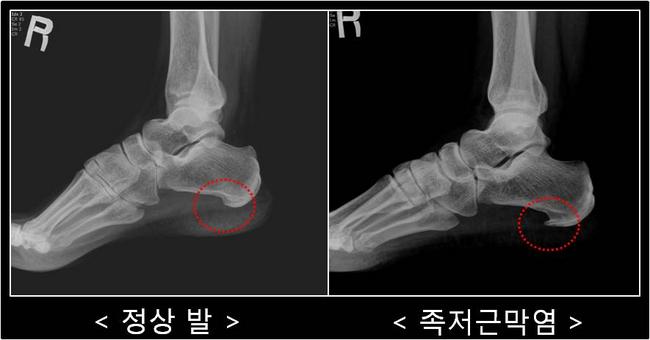

겨울철 기온이 떨어지면 발뒤꿈치 통증을 호소하는 이들이 크게 늘어난다. 특히 아침에 일어나 첫 발을 디딜 때 “발바닥이 찢어지는 듯하다”고 표현하는 경우가 많은데, 이는 족저근막염 초기 증상으로 잘 알려져 있다. 계단을 내려가거나 오랜 시간 서 있을 때 통증이 갑자기 심해지는 것도 특징이다. 전문가들은 이를 방치할 경우 만성 통증으로 이어질 가능성이 높아 조기 관리가 필요하다고 강조한다.

족저근막은 발뒤꿈치뼈에서 발가락 기저부까지 이어지는 강한 섬유 조직으로, 발의 아치를 유지하고 보행 시 충격을 흡수하는 핵심 구조다. 장시간 서 있거나 과도하게 걷는 생활이 반복되면 이 조직에 미세 손상이 쌓여 염증이 발생한다. 최근에는 스마트폰과 PC 사용 증가로 종아리와 아킬레스를 이루는 근육·건이 짧아지면서 발의 하중 분산이 어려워지고, 이로 인해 증상이 악화되는 사례도 보고되고 있다.